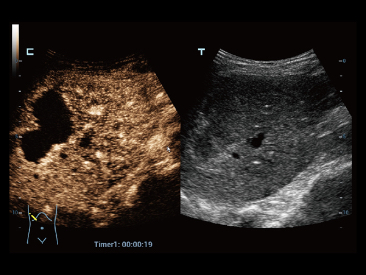

Sejak didirikan, Mindray terus mencari cara baru untuk meningkatkan keandalan diagnostik. Didukung Teknologi ZONE Sonography? terkini, platform ZST+ baru Resona 7 meningkatkan kualitas gambar ultrasound melalui pengambilan zona dan pemrosesan data saluran.

Selain kualitas gambar premium, Resona 7 juga meningkatkan kemampuan penelitian klinis dengan V Flow revolusioner untuk evaluasi hemodinamika vaskular, serta pengambilan penampang tercanggih dari rangkaian data 3D untuk diagnosis CNS pada janin. Kombinasi pengoperasian multisentuh berbasis gerakan yang paling intuitif dengan semua fitur klinis penting membuat Resona 7 menjadi gebrakan baru dalam inovasi ultrasound.